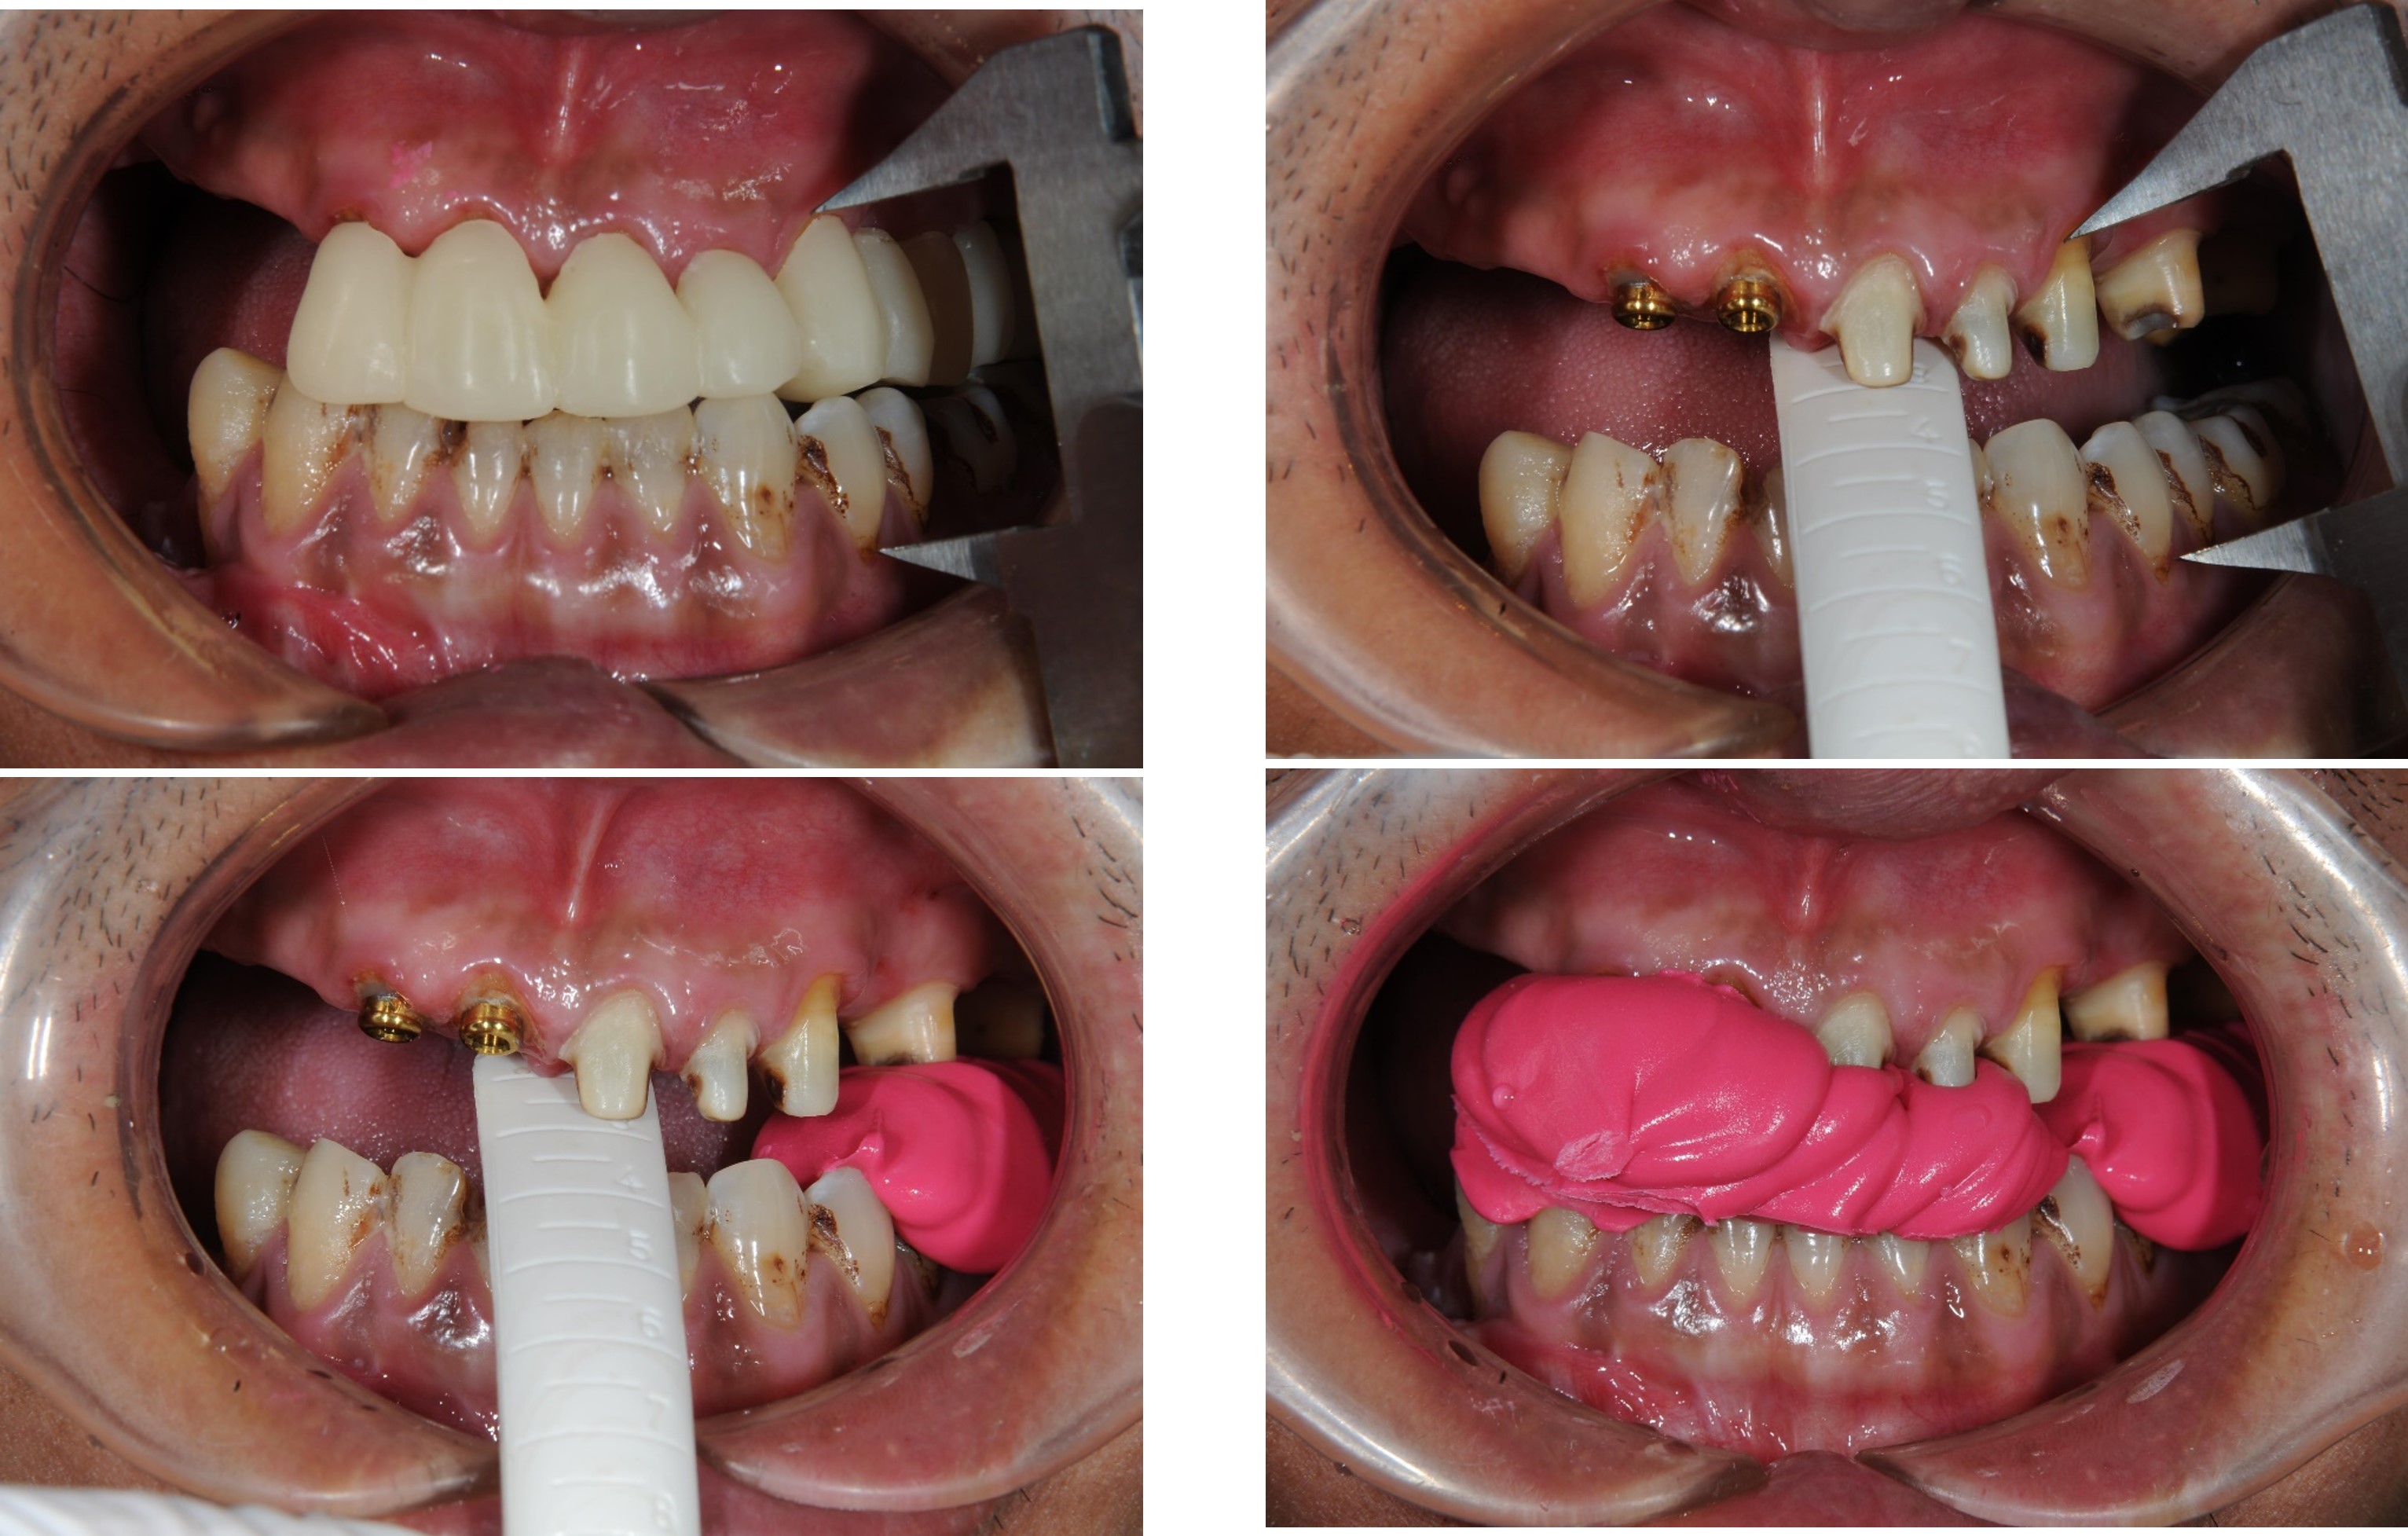

治療前上下顎因口外手術,造成咬合喪失

治療前,咬合喪失,磨耗

上下顎初步印模

咬合記錄